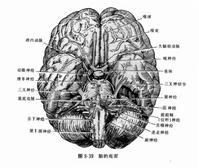

腦室結構圖腦脊液漏好發於顱底骨折,顱前窩骨折常致鼻漏,顱中窩骨折多為耳漏 其原因可能因顱底骨質較薄、硬腦膜貼附緊密;顱前窩有篩板,篩竇、額竇及蝶竇與鼻腔相通;顱中窩有岩骨內含中耳鼓室,外接耳道內通耳咽管;顱底又鄰近腦池,故而較易引起腦脊液漏。與此相反,在兒童由於顱骨較軟、富於彈性,且鼻旁竇尚未發育完全 因此 兒童的外傷性腦脊液鼻漏發生率不足1%。不過,小兒的鼓室、乳突氣房發育較早,故腦脊液耳漏並不少見,另外,因顱腦穿透傷所引起的腦脊液傷口漏(皮漏),常為早期清創處理不徹底,硬腦膜的修補不善所致,且較易發生在腦室穿通傷病人。

腦脊液結構圖腦脊液漏發生的時間差異較大,多數於傷後立即出現或於數天內發生,系屬急性期腦脊液漏;但也有少數病人遲至數月甚至數年之後始出現,稱為延遲性腦脊液漏。前者大多數在1周左右自行封閉癒合;後者一旦出現則常遷延不愈,時停時漏,往往導致顱內繼發感染、反覆發作性腦膜炎。延遲性腦脊液漏發生的原因,可能與顱腦損傷後創口局部出血 腦組織水腫,暫時將硬腦膜破孔封堵有關。待血凝塊溶解、吸收,腦水腫消退之後,又可因某些突然升高顱壓的因素,如用力咳嗽、噴嚏等而使薄弱的裂口發生漏液,所幸這類病人並發腦膜炎的病死率較一般腦膜炎病人明顯為低,估計亦與腦脊液漏的引流作用有關。

腦脊液位置圖實驗室檢查: